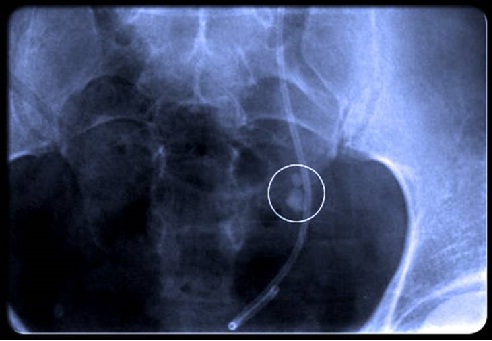

How are kidney stones diagnosed?

The diagnosis of kidney stones is suspected by the typical pattern of symptoms when other possible causes of the abdominal or flank pain are excluded. Imaging tests are

Usually done to confirm the diagnosis. A helical CT scan without contrast material is the most common test to detect stones or obstruction within the urinary tract. In pregnant women or those who should avoid radiation exposure, an ultrasound examination may be done to help establish the diagnosis.

A helical CT scan without contrast material is the most common test to detect stones or obstruction within the urinary tract.